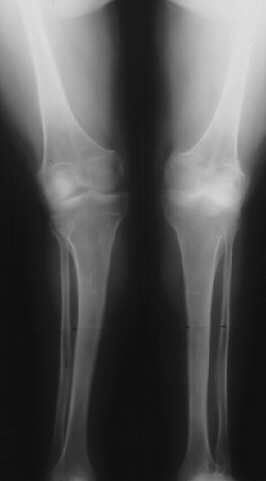

SPONDYLO-EPI-METAPHYSEAL DYSPLASIA WITH JOINT LAXITY (SEMDJL)

Radiographic features: